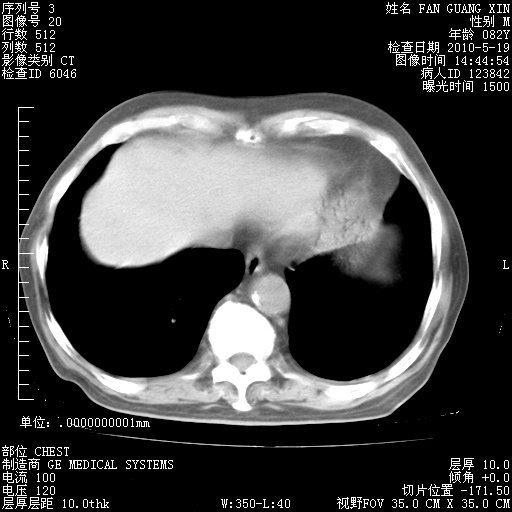

再治疗10天后的肺部CT

再治疗10天后的肺部CT 纵膈窗

阅读此次胸部CT,肺间质渗出性改变较入院时有吸收。目前从体温、白细胞、中性分叶明显增高,肯定存在细菌感染(发生医院感染哦,若无消化道及泌尿系统等感染的依据,肺部感染可能大)。若你院头孢哌酮舒巴坦钠耐药率较高,同意你的方案,若48小时体温仍高,可考虑使用碳青霉稀类抗菌药物,同时可予超声雾化、注意滴数时加大液体量。白蛋白33.30g/L较低哦,需加强营养等支持治疗。